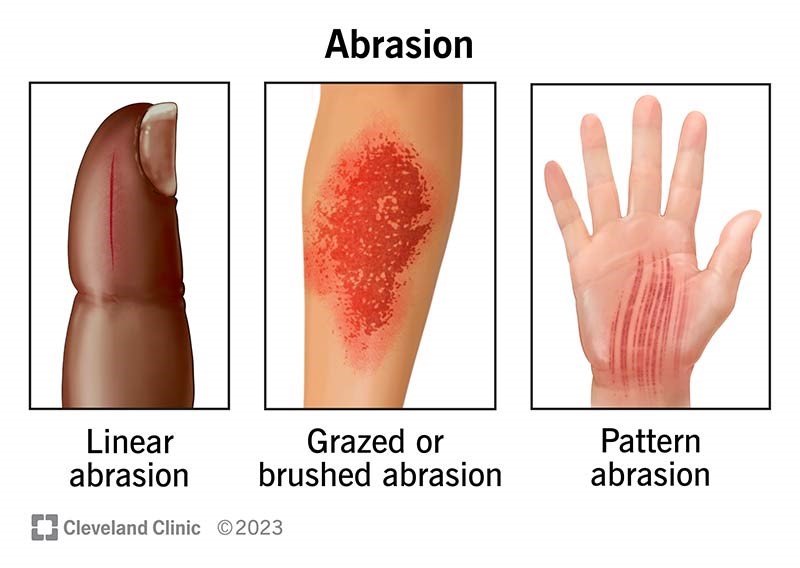

Assists with superficial injuries that occur on the skin and visceral

linings of the body, disrupting tissue continuity.